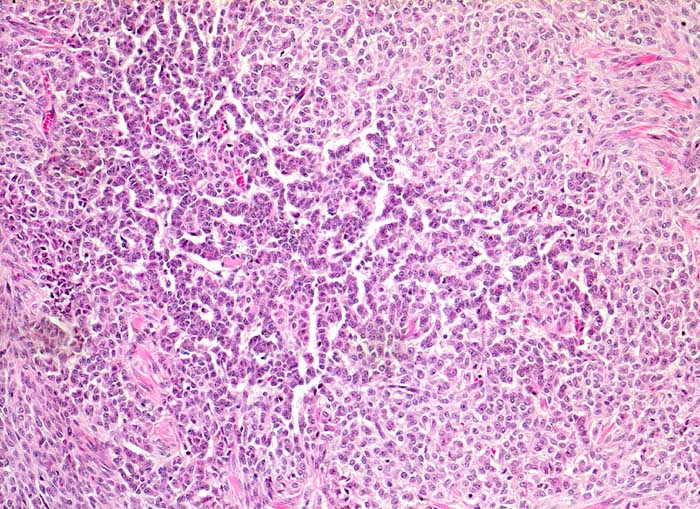

Granulosazelltumor des Ovars

maligner Tumor

Ovar

Morphologie